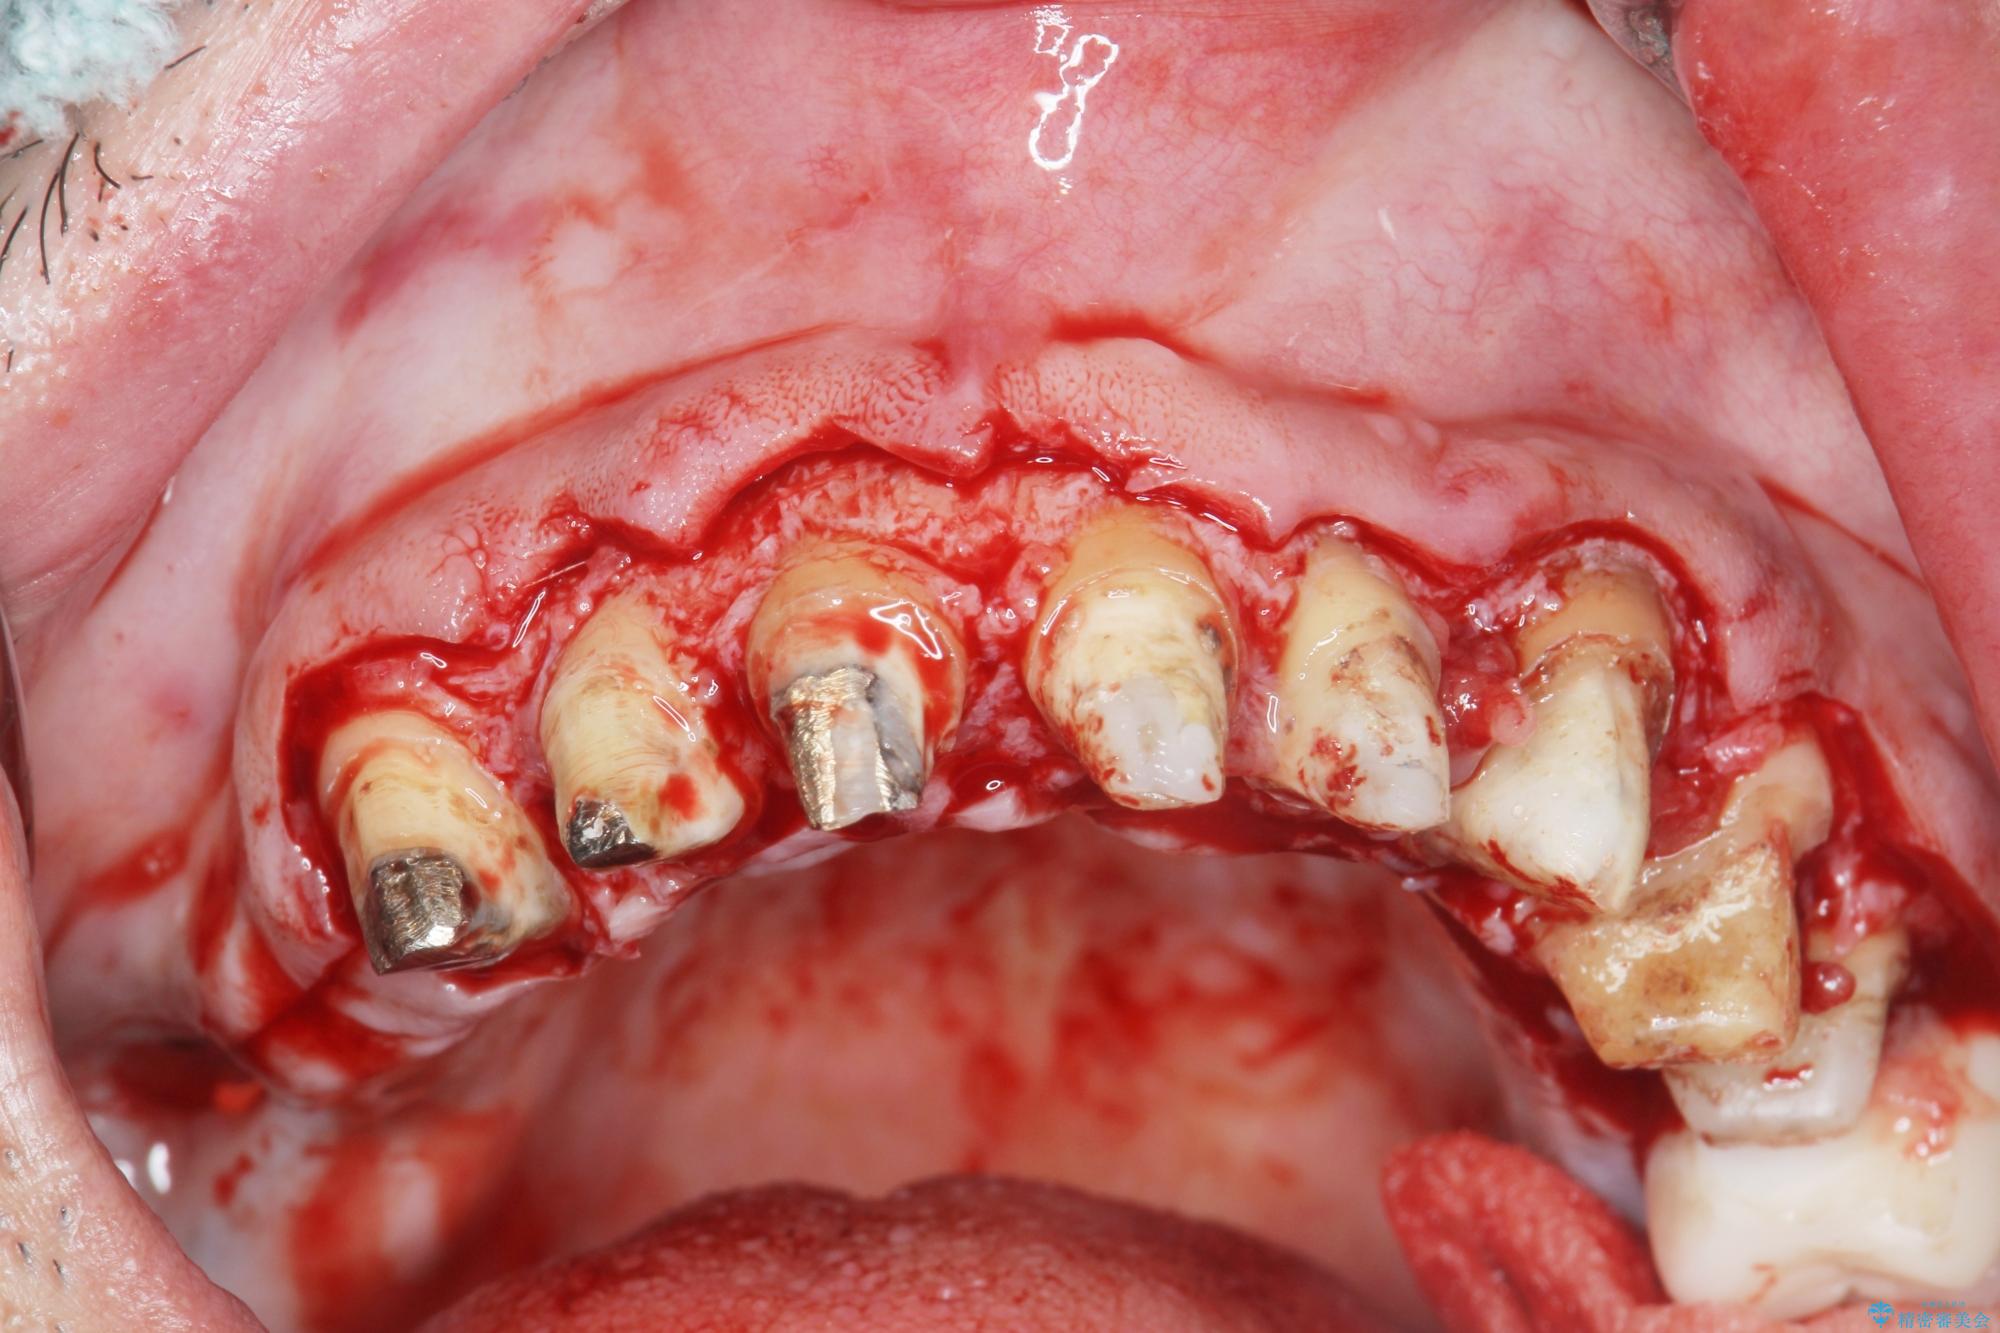

- 「セラミック治療を他院で受けたが、それ以来歯ぐきが腫れ違和感がある、改善してほしい。」と歯ぐきの状態改善を希望され来院されました。

歯周組織検査を行うと歯ぐきからは容易に出血し、X線検査より歯とセラミッククラウンの適合が悪い(ピッタリと合っていない)状態が示唆され、歯ぐきの炎症を惹起している状態でした。

セラミッククラウンを除去し仮歯を装着し、歯周外科手術を行い歯ぐきの状態を改善したのち、適合の良いセラミッククラウンを再作製をする治療計画としました。